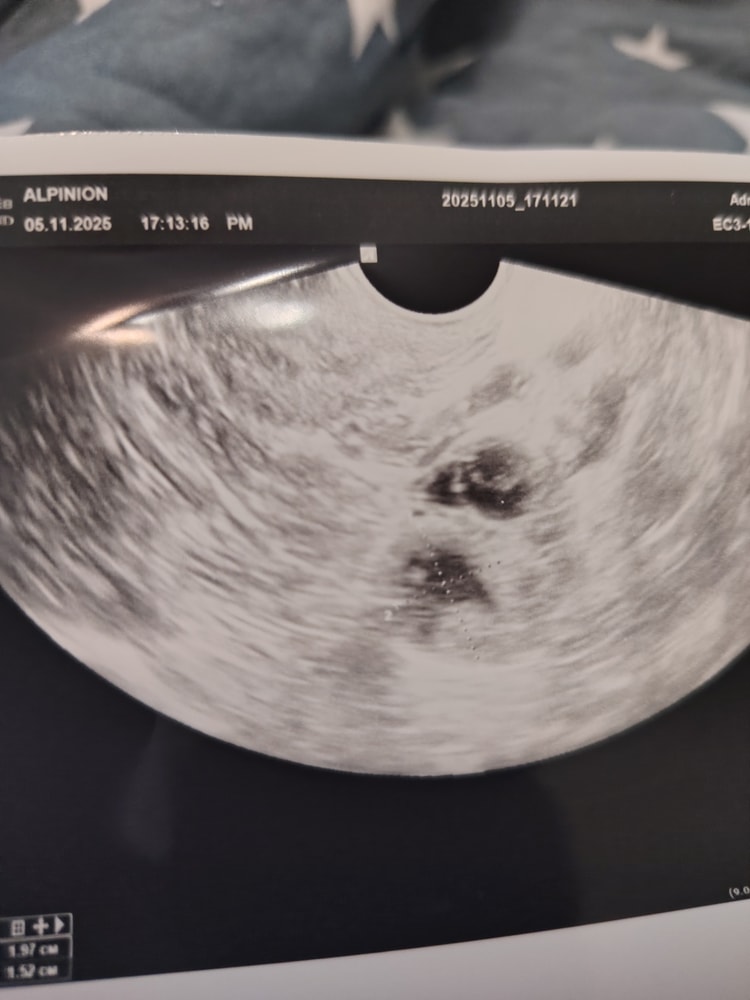

Просмотрите пожалуйста есть ли жёлтое тело на снимке? Нормально ли оно? В заключении написали 15на19 мм.

Мамаша, Вы путаете фолликул с желтым телом. Есть фолликул, который созревает и из него выходит яйцеклетка, на месте этого фолликула образуется желтое тело, которое вырабатывает прогестерон, который, в свою очередь, нужен для развития беременности, если она наступит.

Фолликул может «перезреть», как правило он лопается, дорастая до 24 мм. Если он больше, то это уже киста и овуляции скорее всего не будет.

Судя по вашему узи, у вас фолликул как раз таки лопнул, что говорит об овуляции.